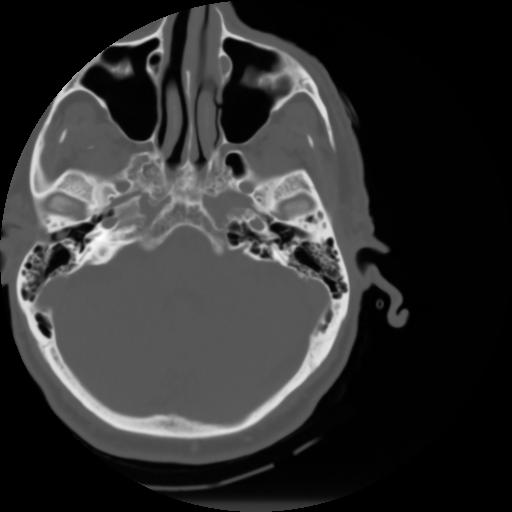

3 CEREBRO,,Axial,3.0,CEREBRO,,